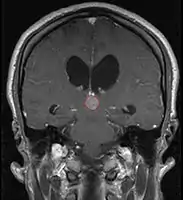

Pineal Gland Tumors

- Work-up includes MRI, CSF, serum markers for bHCG and AFP

- Tissue diagnosis is critical, since management varies significantly based on pathology

- Stereotactic pineal gland biopsy

- Open surgery (typically not favored since only few tumors are amenable to complete resection, many are chemo-RT sensitive, and there is a real risk of worsening visual deficits)